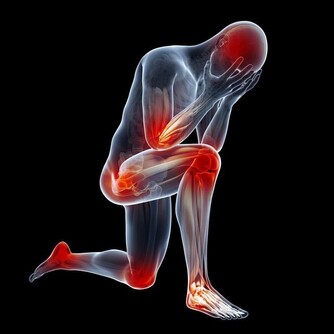

甲狀旁腺被拿掉了,必然影響全身鈣質的吸收,就要終生補鈣。長期缺鈣對身體的影響是巨大的,甲狀旁腺的功能是強大的,損失了它,代價是巨大的。短時間的血鈣低身體就會發麻,抽搐,長期的缺鈣會導致骨密度降低,引起骨質疏鬆,你就是那個一碰就碎的玻璃人。輕輕的一個跟頭,就能斷了胳膊腿。

萬幸我的個子是長起來了,165cm,算是中等個了。由於無知,上大學時偷偷停了半年的藥,我就是不想終生服藥,想看看停藥有什麼不行的。半年後,甲減的症狀越來越明顯了,出現了思維跟不上的情況,明顯反應遲鈍。更壞的結果很快就來了,在一次體育跳遠課上輕輕的一跳,就跳成了左腿脛骨粉碎性骨折,打了一個月石膏。後來經過一年的康復鍛煉,腿才又恢復了。我從骨折後有開始恢復服甲狀腺素片了。甲狀腺癌復發有可能是從那時開始的。

在去年的第二次手術,做右側甲狀腺摘除時就把甲狀旁腺也摘除了。這下我的身體就一點甲狀旁腺都沒有了。它的反應非常明顯,而且迅速。手術當晚就因血鈣的迅速流失,腰椎疼了一晚上,直到第二天早上醫生查房後,給我靜脈注射了葡萄糖酸鈣,才止住了疼。